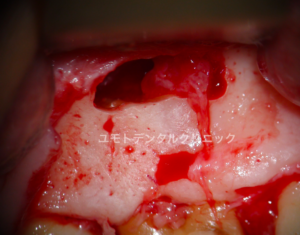

根管治療後も長引く痛みや症状、根尖性歯周炎という病気が治ってこない場合、歯内療法専門医は外科的歯内療法(多くは歯根端切除術)を行っていきます。

本ケースでは、患者さんも根尖性歯周炎により自発痛、咬合痛を主訴とされていました。

患者さんともよく相談をさせていただき、今回は次点の策として歯根端切除術を行うことになりました。

歯肉剥離、骨開窓

根尖部肉芽様組織除去

歯根端切除面

逆窩洞形成、充填後

術前のレントゲンで確認される不透過像(遠心根根尖部の破折ファイル片)は逆窩洞形成時に除去しております。

画像に確認される止血用の綿球は処置完了後に除去しております。

術後、補綴医の先生に歯冠補綴を行っております。

幸いにも症状の消失、根尖性歯周炎の治癒傾向を確認できております。